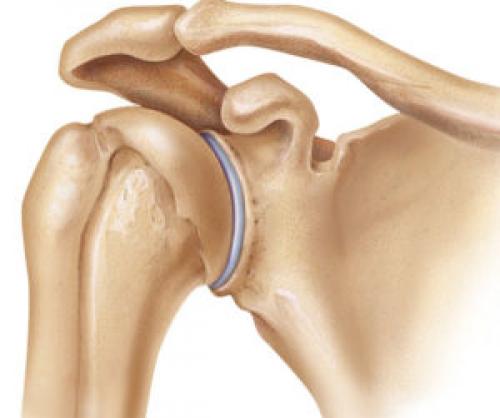

Суставы верхних конечностей устроены таким образом, чтобы обеспечивалась максимально возможная амплитуда движений. Рука здорового человека без особого труда отводится в сторону и назад, поднимается вверх и при этом может отклоняться назад. Все эти движения не доставляют никаких неприятных ощущений. Но только в том случае, если все ткани суставов находятся в нормальном физиологическом состоянии. К сожалению, большая подвижность приводит к истончению хрящевой ткани, уменьшению количества синовиальной жидкости, механическим травмам сухожильной ткани связочного аппарата.

У ребенка щелкает плечевой сустав. Остеоартроз

Плечевой сустав щёлкает при остеоартрозе — дегенеративно-дистрофической патологии. Её развитие провоцируют эндокринные и метаболические нарушения, предшествующие травмы, интенсивные физические нагрузки и низкая двигательная активность. В сочленении начинают разрушаться хрящи, выстилающие поверхности костных головок. Это приводит к разрастанию краёв костных пластинок и формированию остеофитов (наростов) . Они давят на нервные окончания, расположенные поблизости мягкие ткани. Постепенно гиалиновые хрящи истончаются, утрачивают свои амортизационные свойства. Суставная щель частично ил полностью сращивается, плечо обездвиживается. Клиническая картина остеоартроза состоит из таких характерных признаков:

- боли, усиливающиеся при вращении плеча и практически исчезающие на конечной стадии патологии;

- утренняя припухлость сустава и скованность движений ;

- щелчки, возникающие при смещении костных головок на фоне истончения хрящевых тканей.